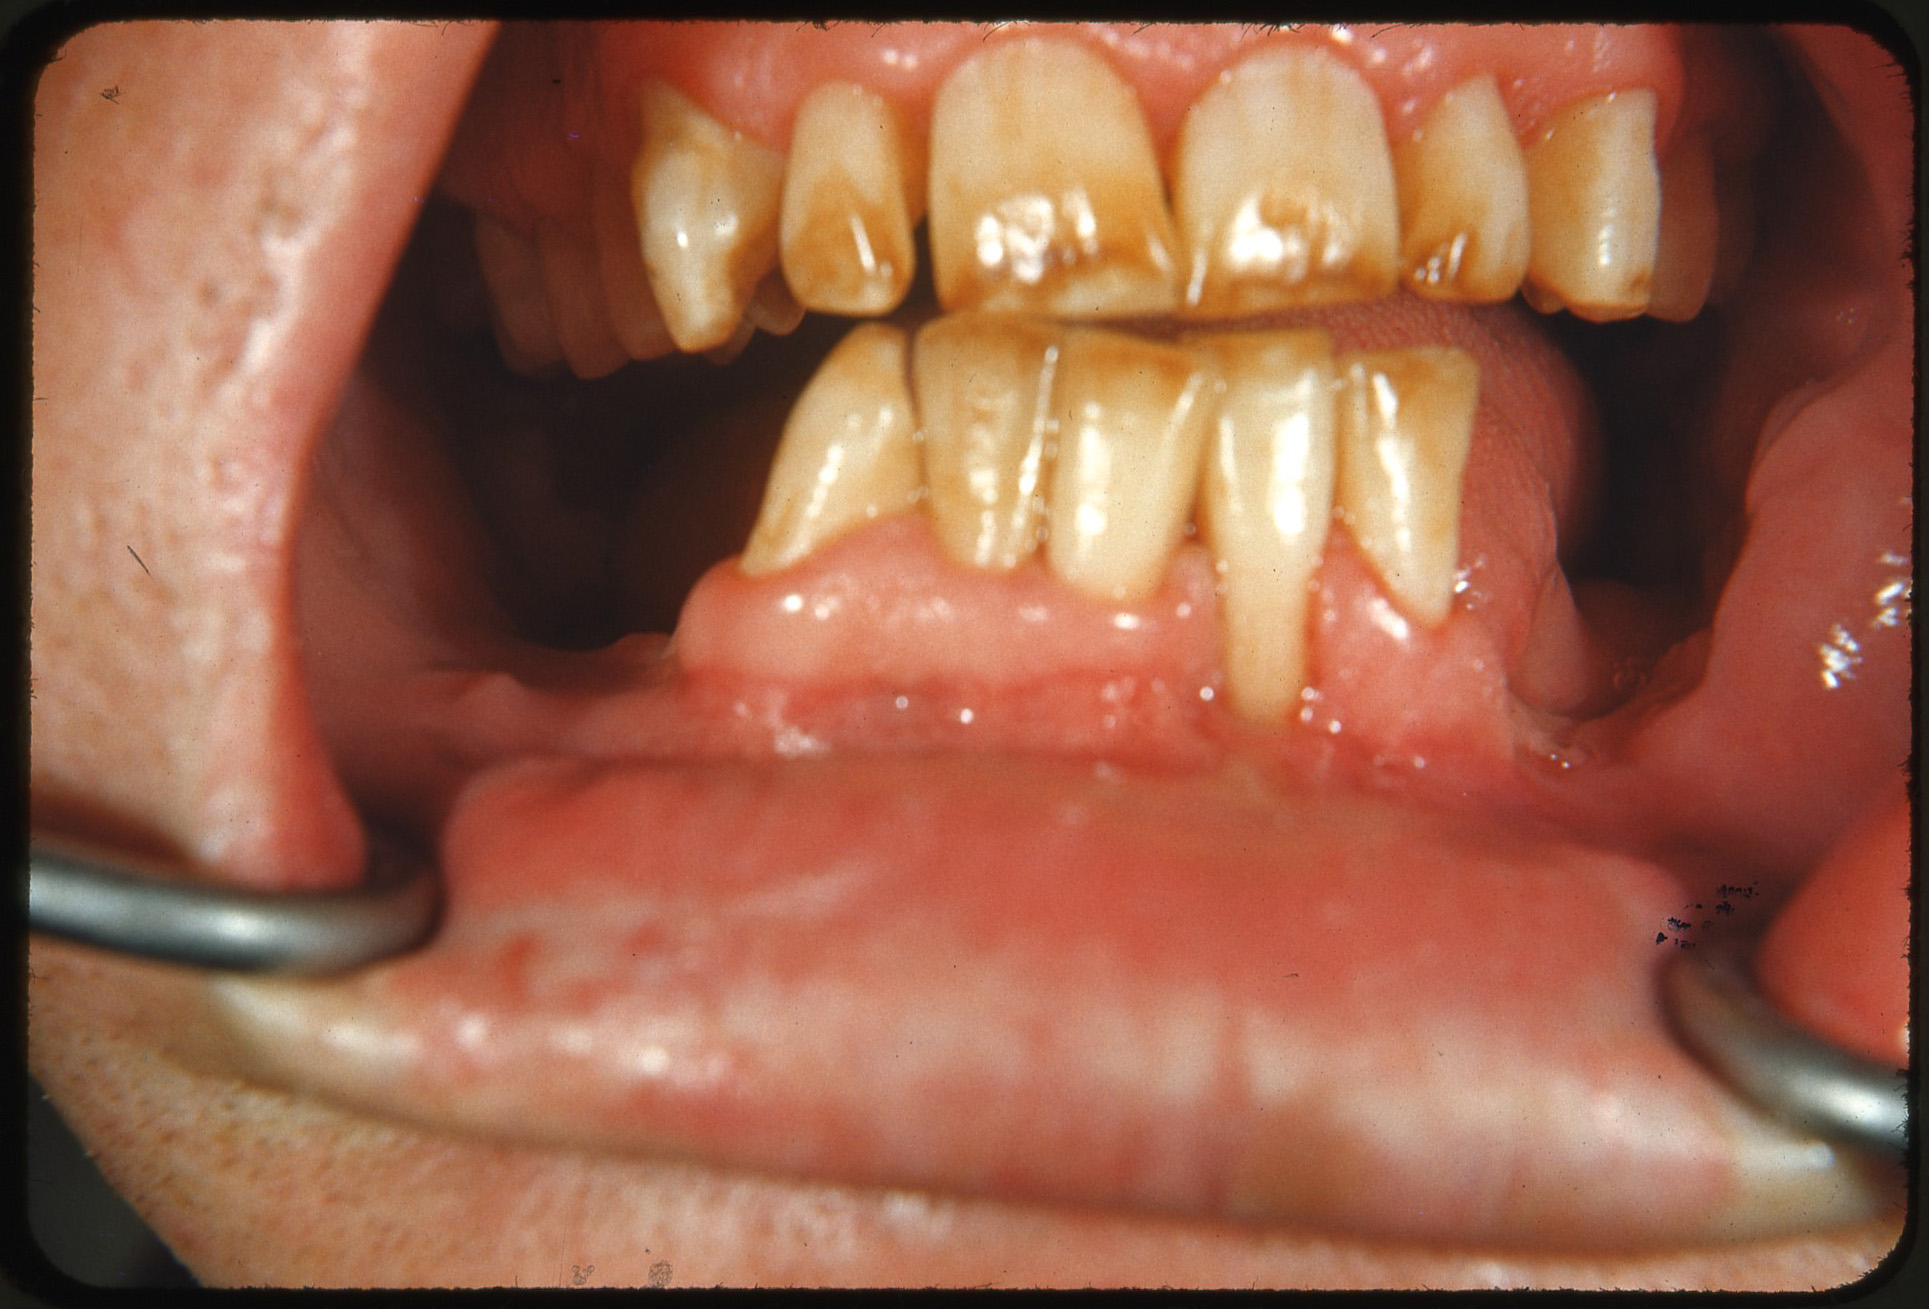

경미한 반상치의 경우, 치아 법랑질 표면은 대체로 손상되지 않고 단단하며 매끄럽지만, 경계가 불분명한 불투명한 흰색 반점이나 주름선(perikymata)을 따라 좁은 흰색 선이 나타나는 특징을 보인다.[7] 상태가 심해질수록 치아 표면 아래의 법랑질은 더욱 다공성(구멍이 많아지는 상태)이 된다. 이로 인해 법랑질은 황색이나 갈색으로 변색되거나, 충치와 유사하게 움푹 들어간 흰색-갈색 병변이 여러 개 나타날 수 있다. 이러한 외형은 흔히 "얼룩덜룩한 치아"라고 묘사된다.[8]

반상치 자체가 직접적으로 치아 변색을 일으키는 것은 아니다. 반상치의 영향을 받은 영구치가 처음 입안으로 나올 때는 아직 변색되지 않은 상태이다. 반상치는 법랑질 표면 아래에 미세한 구멍(다공성)을 만들거나 저석회화를 유발하는데, 상태가 진행되면 이러한 변화가 상아질-법랑질 경계면까지 확장된다. 이렇게 다공성이 증가한 법랑질은 외부 물질에 의한 착색에 더 취약해진다. 시간이 지나면서 음식물이나 음료 등에 포함된 외인성 이온(예: 철, 구리 이온)이 비정상적으로 다공성이 된 법랑질에 침투하여 점차 얼룩을 만들게 된다.[7]

반상치는 치아가 발달하는 시기에 불소를 과다 섭취하여 법랑질 형성에 이상이 생기는 질환이다.[13] 과도한 불소는 법랑질의 정상적인 광화 과정을 방해하여 표면 아래가 저석회화되고 다공성 구조를 띄게 만든다.[7] 이로 인해 치아 표면에 흰색 반점이나 줄무늬가 나타나며, 심한 경우 황갈색으로 변색되거나 표면이 패일 수 있다.[7][8] 이러한 변화는 주로 영구치에 나타나며, 시간이 지남에 따라 외부 물질에 의해 착색될 수 있다.[7]